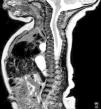

RM posnatal: extensa lesión quística bilobulada del mediastino posterior con trayecto fistuloso hasta el cuerpo vertebral de D3. Se objetiva pinzamiento D3-D4 y pequeña escotadura central en el platillo inferior de D3 y superior de D4, sin comunicación con el canal raquídeo ni alteraciones medulares, compatible con quiste neuroentérico.